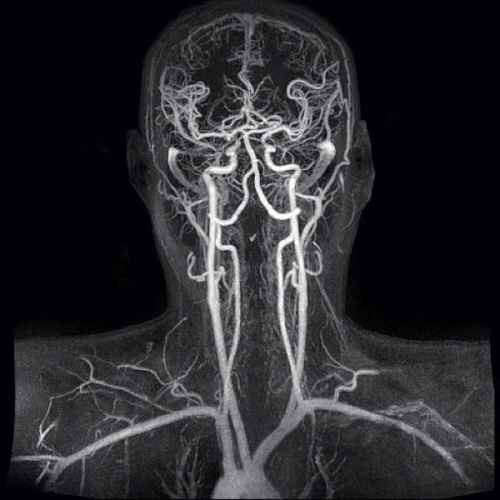

Диагностировать заболевания сосудов к в медицинских центрах СПб можно с помощью методов аппаратного обследования — УЗИ, КТ и МРТ. Так, ультразвуковое исследование позволяет врачам хорошо визуализировать атеросклеротические бляшки, стенозные поражения сосудов по всей длине ноги или руки, шеи и определять степень кровотока, степень окклюзии. УЗИ дуплексное, триплексное сканирование сосудов помогает визуализировать состояние как артерии, так и вены.

А вот МРТ сосудов лучше показывает начальные стадии воспалительных и опухолевых сосудистых заболеваний.

На КТ и МРТ ангиографии будут хорошо отображены даже мелкие артерии и вены. Это более детальная и точная форма диагностики. По своей информативности МРТ и КТ сопоставимы.

В отличие от компьютерной томографии МР-диагностика не использует излучение, а с помощью магнитного поля и радиоволн показывает состояние сосудистого русла и кровотока. Поэтому с точки зрения безопасности, МРТ сосудов лучше, чем КТ.